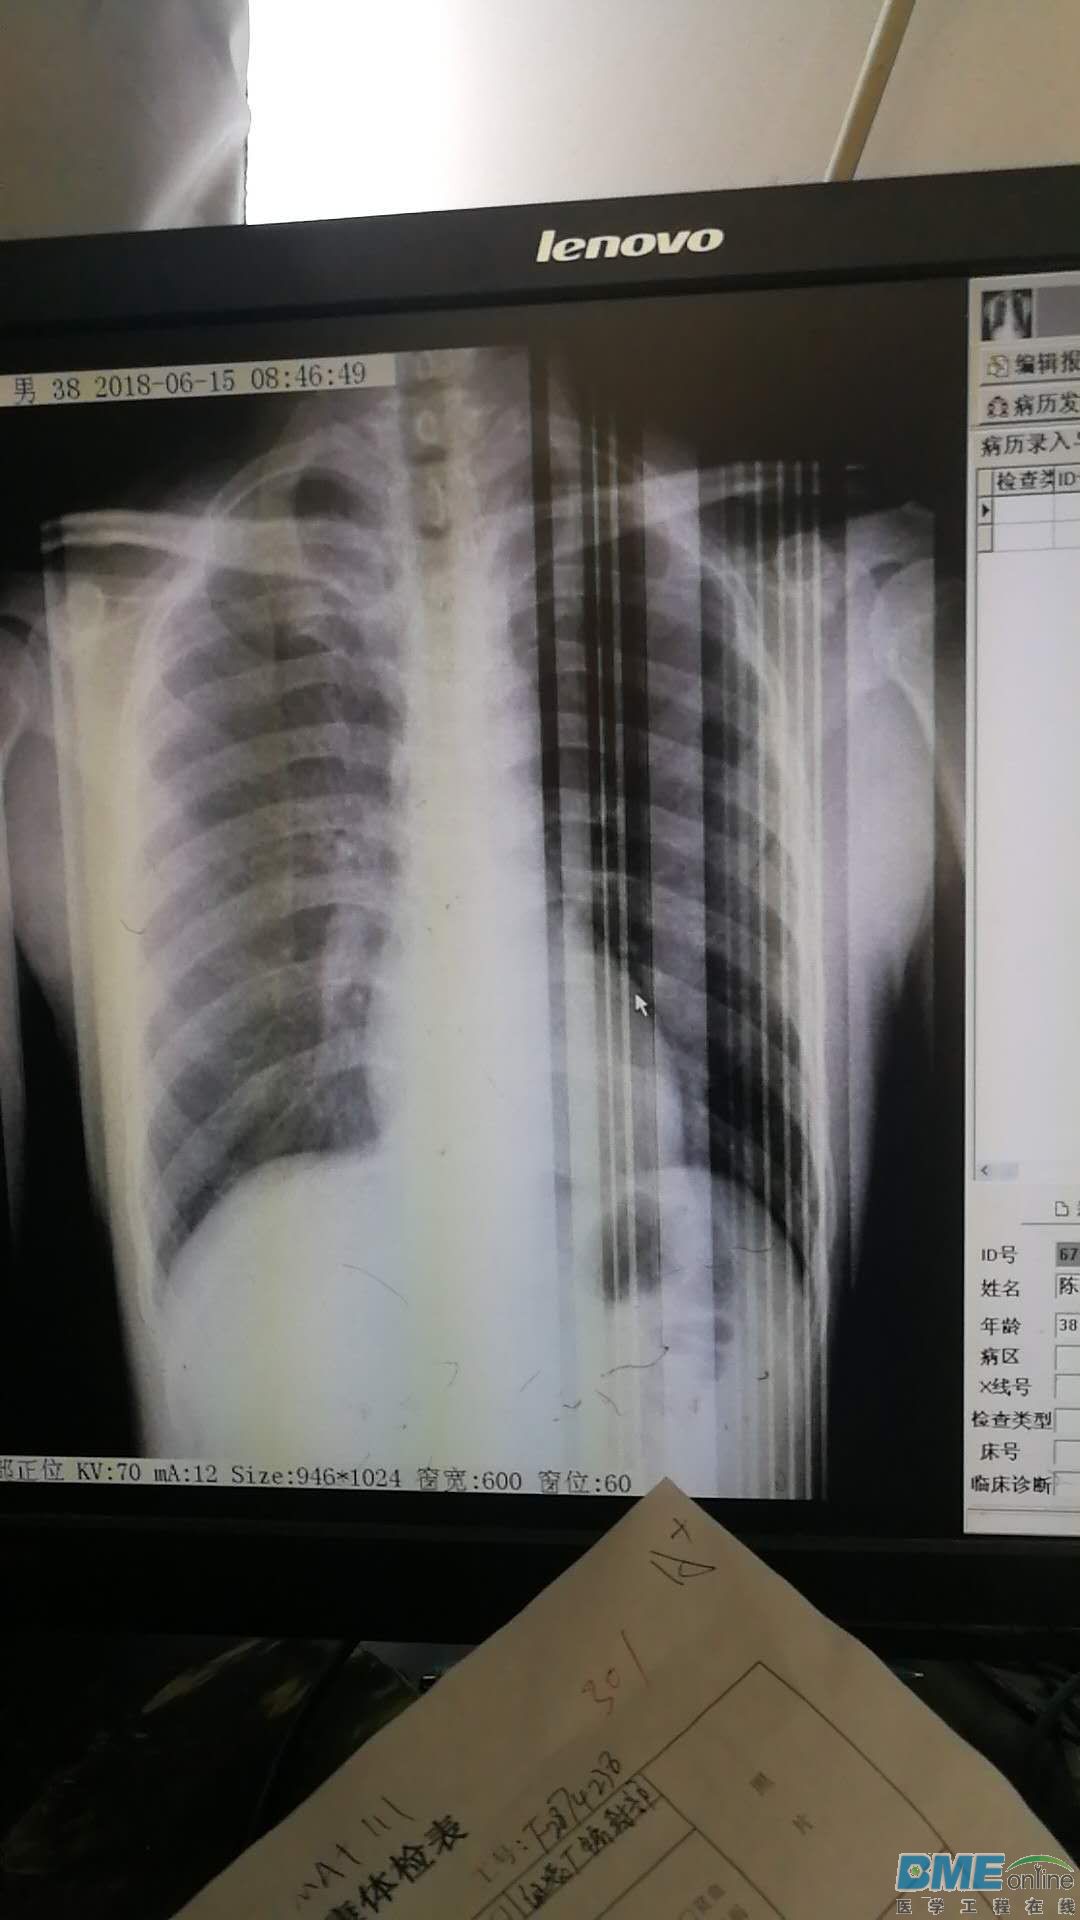

图像有时出现不规则的竖条

图像有时出现不规则的竖条,出现时机没有一定规律。有时几天不出,有时当天早晨开机就出现,也许待机一会,又不出了。

航天中兴 线扫描

平板需要校准,或者平板出问题了’

为什么不可以是显示器问题呢

显示器先拿到别的主机上去试试,很容易检查出来是否是显示器问题

平板探测器坏了